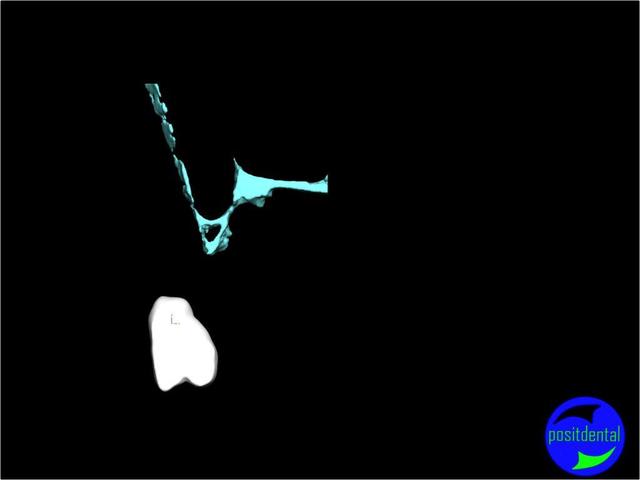

une autre vue du photshopman:

modèle stéréo du à la gentillesse de Posit